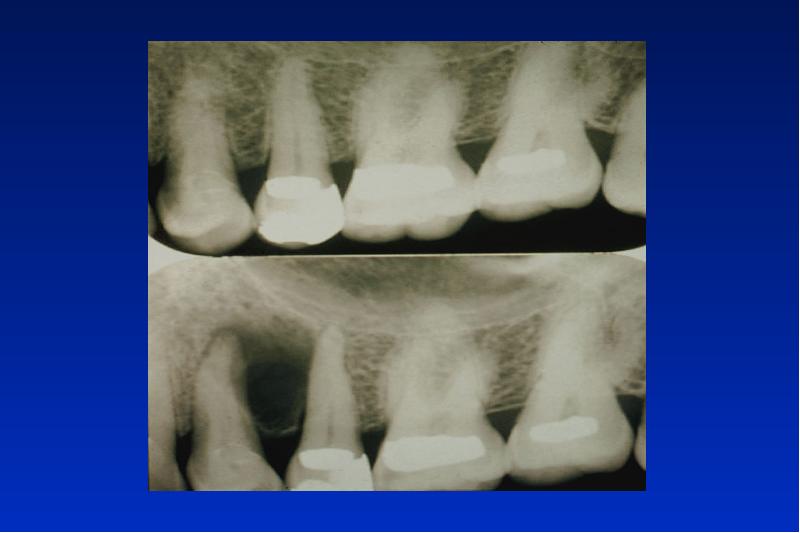

- 77. Periapikale zemento-ossäre Dysplasie benigne nicht neoplastische selbst limitierende Läsion ohne Kapsel

- 79. Floride zemento-ossäre Dysplasie (gigantoformes Zementoblastom) benigne nicht neoplastische Läsion mit